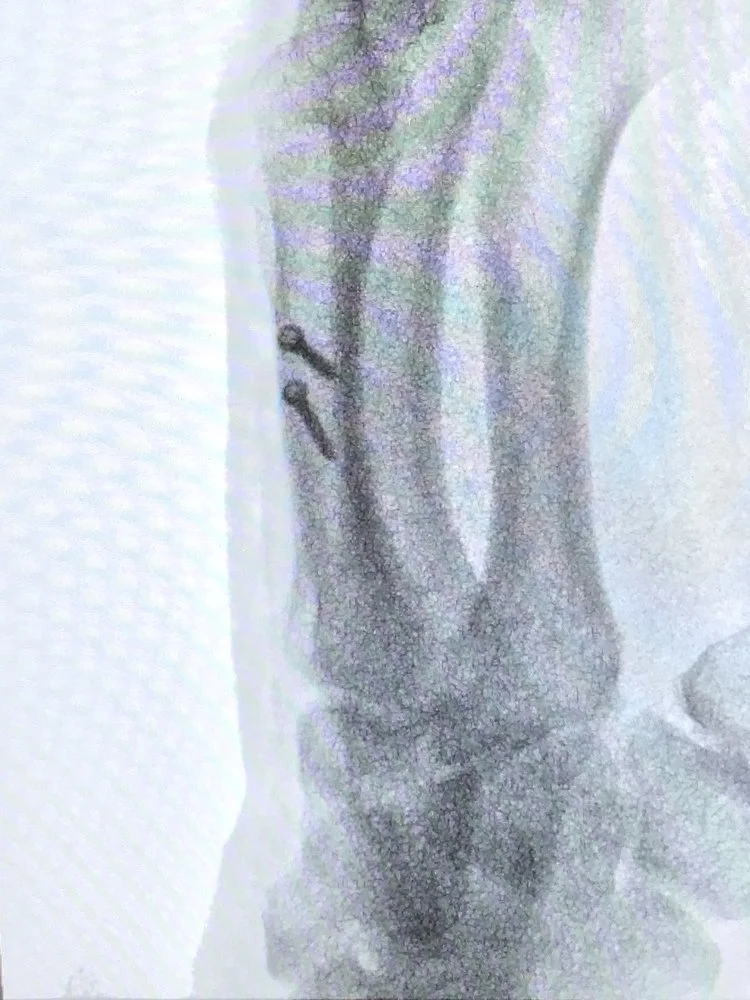

Metacarpal Fracture